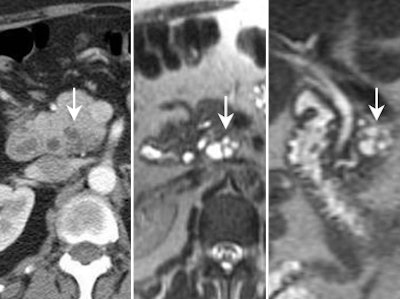

![]() |

| Mucinous cystadenocarcinoma. Presence of mural calcifications (arrow) and septations are suggestive of malignancy. |

| MRI demonstrating mucinous cystadenoma in tail of pancreas (arrow). On T2-weighted images the cyst fluid has high signal intensity similar to CSF. |